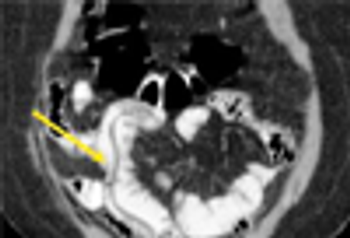

The authors present a case of rupture of the rectus abdominis muscle with subsequent rectus sheath hematoma-an uncommon and often misdiagnosed cause of acute abdominal pain.

Emphysematous cholecystitis is a rare condition that is the result of infection with Clostridium perfringens and other gas-producing organisms including Escherichia coli, Bacteroides fragilis, and Klebsiella species.

Emphysematous cholecystitis is a rare condition that is the result of infection with C perfringens and other gas-producing organisms including Escherichia coli, Bacteroides fragilis, and Klebsiella species.